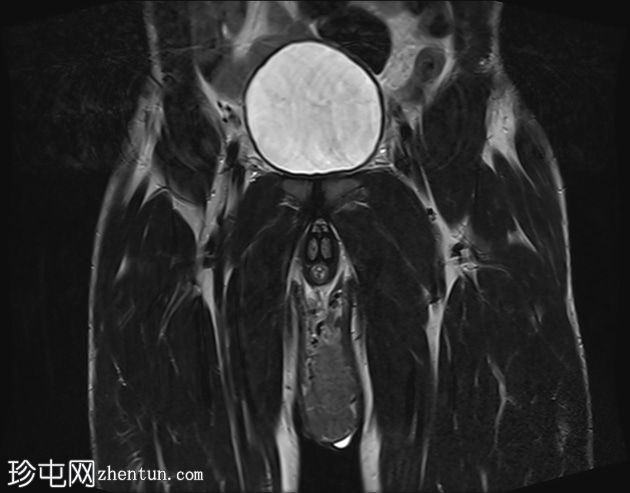

冠状位

T2加权像

阴囊内睾丸增大,T1加权像上可见分叶状软组织病变,呈中高信号,T2加权像上呈低信号。

轻度双侧鞘膜积液。

本病例表现为双侧睾丸肿胀,影像学特征符合睾丸肾上腺残余肿瘤的典型表现,即T1加权像上呈双侧中高信号,T2加权像上呈低信号。